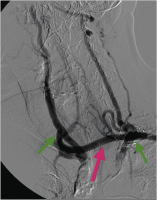

Angiographie

Abbildung 2: Postoperative Angiographie: Bypass (roter Pfeil) von der linken Art. subclavia (peripher des Abgangs der Art. vertebralis, grüner Pfeil) auf die rechte Art. carotis communis (grüner Pfeil).